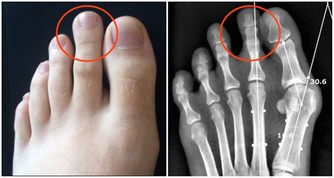

3、懶得上廁所

到了冬天,暖呼呼的被窩裡,似一隻手緊緊拽著你,讓你別離開。尿意來時,不少人會犯懶,選擇憋一憋。

但這一“憋”,事就大了,不僅容易引起尿路感染,還可能引起腎盂腎炎,損害腎臟,導致膀胱癌。若是早上,人的各項生理功能維持著低速運轉,長時間憋尿易使心腦血管疾病患者發生意外。

★建議:想上廁所就趕緊去,別犯懶,憋坏身子不太不值!